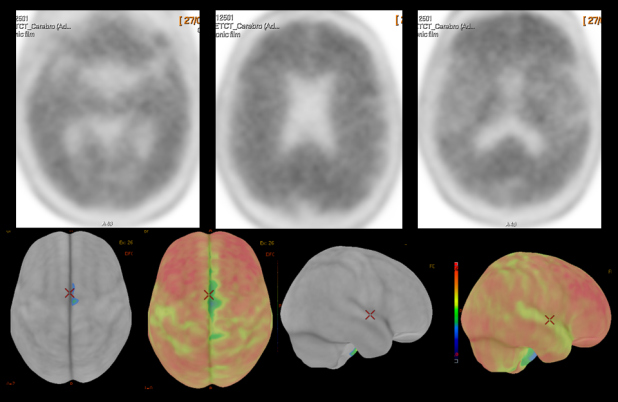

Se complementó con estudio PET Beta- amiloide (18F-Florbetaben). En las imágenes precoces post-inyección que aportan información de la perfusión cerebral, no se apreciaron alteraciones significativas en las diferentes estructuras corticales que conforman ambos hemisferios cerebrales, así como tampoco a nivel subcortical ni en fosa posterior (fig 3). En las imágenes tardías post-inyección que informan sobre la densidad de placa neurítica de beta-amiloide (fig. 4) se observó pérdida de la diferenciación entre sustancia gris y sustancia blanca en todas las regiones claves. La sustancia gris de dichas regiones muestra una importante captación del trazador, superior a la de la sustancia blanca, abarcando la mayoría de los cortes y en algunas zonas llegando incluso al margen cortical exterior. Presenta una puntuación CCRT (captación cortical regional de trazador) de 3. El estudio se considera globalmente como positivo con un CPAE grado 3 (exploración con depósitos importantes de beta-amiloide).

La evolución ratificó el diagnóstico clínico de proceso degenerativo primario tipo DTA, lo cual fue confirmado por una prueba de neuroimagen funcional con SPECT-CT usando 99mTc-HMPAO (fig. 5), practicada a los dos años de iniciar el estudio del paciente.